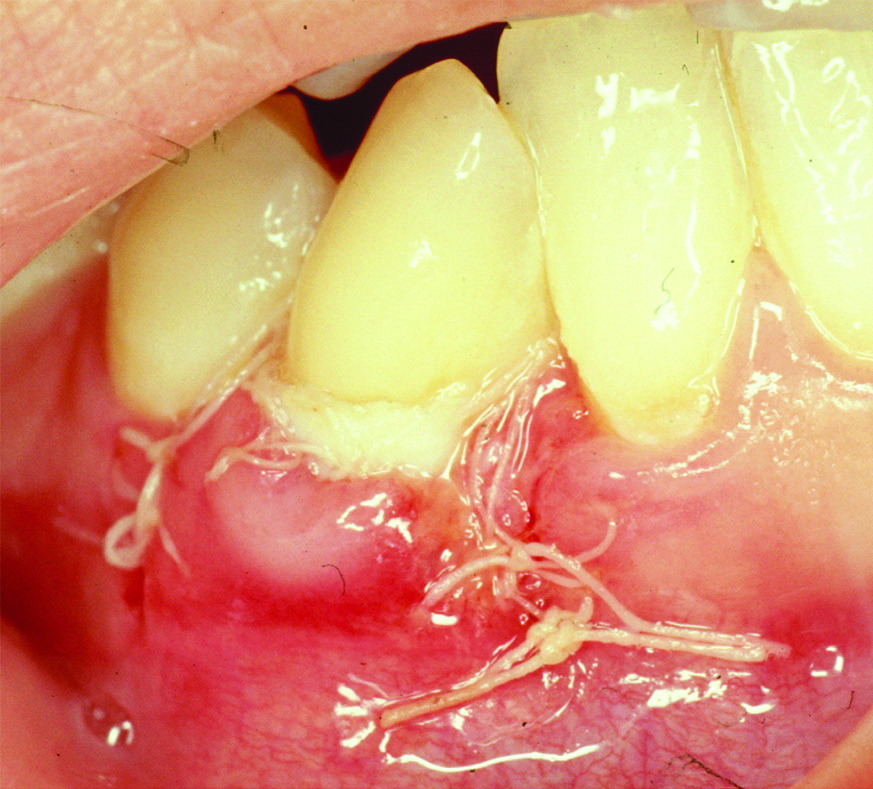

A 36-year-old female patient presented in to the periodontal clinic in 2002 with a complaint of long teeth and sensitivity in the lower right (#43) and left (#33) canines. The dental history revealed that the patient had a history of using an aggressive brushing technique, which caused generalised abrasion of the cervical region and resulted in the placement of a composite restoration to fill the abrasion area. Subsequently, gingival recession occurred in some areas, and root sensitivity reoccurred because of a leakage of these restorations. Clinical examination revealed the presence of gingival recessions of approximately 3-4 mm on teeth #33 and #43, with the presence of a composite restoration on the root surface [Table/Fig-1]. The recession defect was classified as Miller’s Class II, with 1 mm of a keratinised gingiva and no attached gingiva [1]. The probing depth ranged from 1 to 2 mm. The plaque index was 75%, with bleeding on probing of 55%. Phase I therapy consisted of scaling and root planing, with plaque control measures using a modified Stillman’s brushing technique and interdental flossing at home. The surgical phase consisted of removal of the old restoration and replaced with a new restoration which; was contoured to the crown only then, placement of a connective tissue graft, combined with a double-papilla flap. The patient agreed to the procedure and signed informed consent. Prior to soft tissue grafting, the composite restoration was removed from the root surface and contoured to the tooth crown only, and the root surface was smoothed with a finishing bur [Table/Fig-2]. The right side of the palate was used as a donor site, which was anaesthetised with one ampoule of lidocaine, while each recipient site received two ampoules. Blade #15 was used for incision placement and palatal tissue harvesting. Two oblique incisions of 3 mm long were placed on each side of the tooth, with two vertical incisions extended beyond the mucogingival junction. A partial thickness flap was utilised all the way long [Table/Fig-3]. A connective tissue graft of 13×5 mm, with 2-mm thickness after removal of adipose tissue, was harvested from the palate, and the donor site was secured with a 4-0 vicryl suture [Table/Fig-4]. The graft was divided in half, for teeth #33 and #43, respectively. The graft was then, sutured in place with a 5-0 vicryl suture using a simple interrupted technique; then, a double-papilla rotational flap was secured with 5-0 vicryl [Table/Fig-5]. No periodontal dressing was used. Postsurgical medication consisted of ibuprofen 400 mg/qid for four to seven days and rinsing with normal saline twice daily for seven days. The patient was instructed to eat soft food for seven days. Brushing of the surgical site was deferred for six weeks, and the patient was asked to use a cotton tip with mouthwash to clean the area twice daily. The sutures were removed after two weeks, and the healing was uneventful, with no complications [Table/Fig-6]. Since the patient had mild localised periodontitis, with a history of an aggressive brushing technique, she was placed on a maintenance recall every four months for suppurative periodontal therapy.

Slight sloughing of the coronal part of the graft on tooth #43 after two weeks of healing.